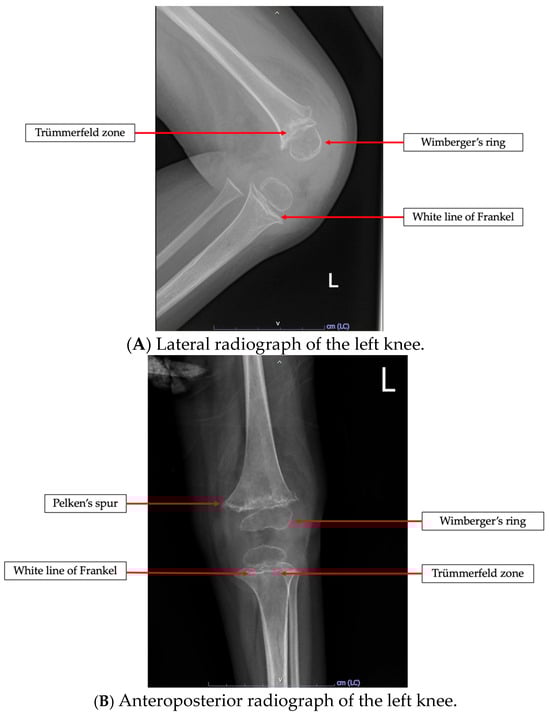

3.4. Radiological Study